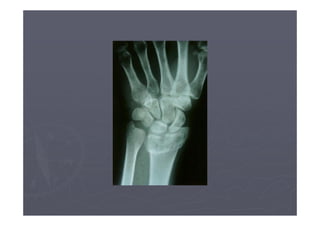

►Menos de 10% de fraturas da parte distal

do antebraço ou fraturas do quadril são

diagnosticadas ou tratadas como

osteoporose.

►Tratamentos sintomáticos prevalecem.

DENSITOMETRIA ÓSSEA

► A maneira mais comum de uma pessoa descobrir

que está com osteoporose é quando ela fratura o

quadril ou o punho após uma queda sem maiores

proporções.